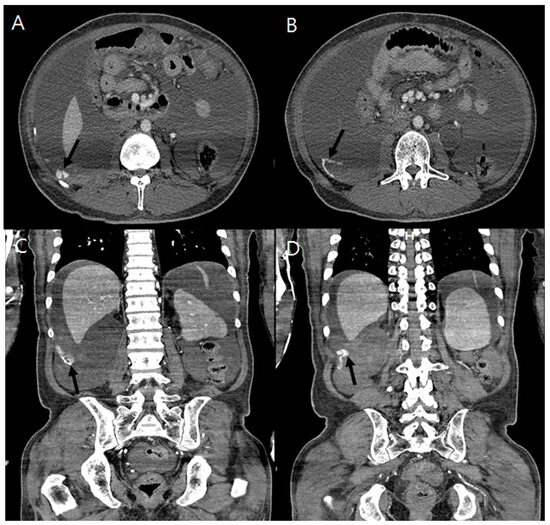

Sinus tachycardia was shown on electrocardiography. His initial laboratory findings were as follows: leukocyte count, 5.56 × 109/L (range: 4.0–10.0 × 109/L); hemoglobin, 6.5 g/dL (range: 12–16 g/dL); platelet count, 167 × 109/L (range 130–400 × 109/L); calcium, 8.5 mg/dL (range: 8.8–10.6 mg/dL); phosphate, 4.8 mg/dL (range: 2.5–4.5 mg/dL); blood urea nitrogen, 35.6 mg/dL (range: 8.0–20.0 mg/dL); creatinine, 14.22 mg/dL (range: 0.51–0.95 mg/dL); total protein, 5.3 g/dL (range: 6.6–8.7 g/dL); albumin, 3.1 g/dL (range: 3.5–5.2 g/dL); total bilirubin, 0.56 mg/dL (range: 0.3–1.2 mg/dL); aspartate aminotransferase, 18 U/L (range: 1–37 U/L); alanine aminotransferase, 13 U/L (range: 1–41 U/L); HbA1c, 7.2% (range: 4.2–5.9%); intact parathyroid hormone, 95.72 pg/mL (range: 15.0–65.0 pg/mL); prothrombin time, 15.2 s (range: 11.9–14.3 s); and aPTT, 37.4 s (range: 29.1–43.5 s). No aortic dilatation of the chest and abdomen was observed on computed tomography (CT). An abdominal CT scan showed a large amount of ascites and enhanced dots and an active extravasation of contrast media around the right posterolateral area into the abdominal cavity (Figure 1) without solid organ injury or adjacent bony fracture, which suggested active bleeding.

Figure 1. A contrast-enhanced computed tomography of the abdominopelvis shows extravasation of the contrast medium into the retroperitoneum indicating active bleeding (black arrow) of a vessel near the right posterolateral area and enhancing ascites. Cross section (A,B) and coronal section (C,D).